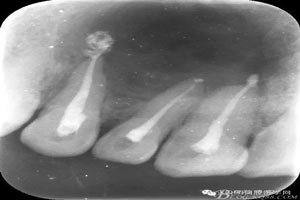

圖1.術前全景片檢查:11、12、13根尖區(qū)橢圓形陰影,邊界清楚,單囊影。初步診斷:頜骨囊腫